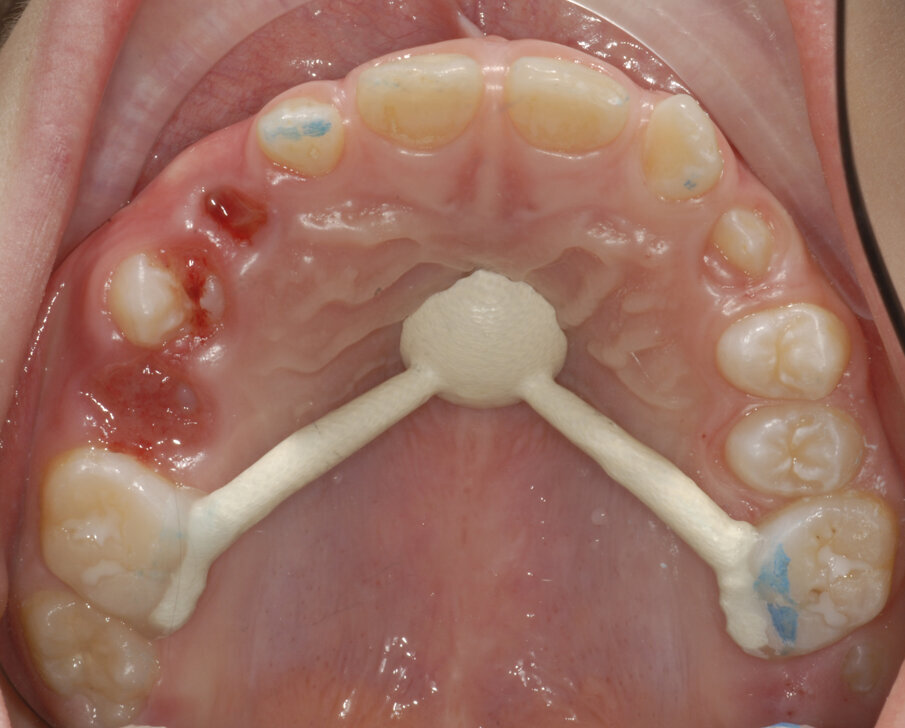

Dopo aver rilevato delle impronte con polivinilsilossano per realizzare un espansore del palato, si esegue l’espansione rapida del mascellare (Figg. 5, 6) superiore con il dispositivo cementato sui secondi molari decidui (5.5-6.5). Al termine dell’espansione, sono rilevate delle nuove impronte con polivinilsilossano per realizzare una barra palatale (Fig. 6) ancorata sui primi molari permanenti (1.6-2.6); viene eseguito un protocollo di estrazioni anticipate dei primi molari decidui e dei canini decidui (Figg. 7-9).

Fig. 9_Estrazione 5.3-6.3.